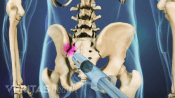

A sacroiliac joint fusion eliminates movement at the sacroiliac joint by grafting the ilium and sacrum together.

Surgical Treatment for Sacroiliac Joint Pain